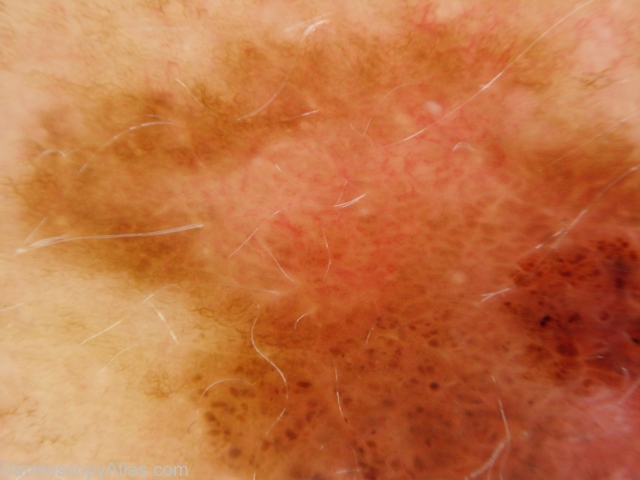

Site: Abdomen

Diagnosis: Melanoma invasive

Sex: F

Age: 54

Type: Dermlite Polarised

Submitted By: Ian McColl

Description: Pigmented lesion on the back showing pigment dots, asymmetry of pigmentation and a negative network.

History: This lesion had developed over several months. It was brought to her attention by being itchy. It was a superficial spreading melanoma, 0.35mm thick , Clark level 2. The histopathology did show some features of regression.